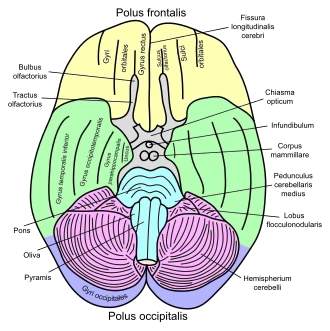

Human brain inferior-medial view (Uncus is #5) | |

The uncus is an anterior extremity of the parahippocampal gyrus. It is separated from the apex of the temporal lobe by a sulcus called the rhinal sulcus.[1] Although superficially continuous with the hippocampal gyrus, the uncus forms morphologically a part of the rhinencephalon.

The part of the olfactory cortex that is on the temporal lobe covers the area of the uncus, which leads into the two significant clinical aspects: herniations and seizures

- Herniations of the brain can occur if increased intracranial pressure due to a tumor, hemorrhage, or edema pushes the uncus over the tentorial notch against the brainstem and related cranial nerves. This can compress the oculomotor nerve (CN III).

This causes problems associated with a non-functional or problematic CN III - the pupil on the ipsilateral side fails to constrict to light and absence of medial/superior movement of the orbit, resulting in a fixed, dilated pupil and an eye with a characteristic "down and out" position due to dominance of the abducens and trochlear nerves. Further pressure on the midbrain results in progressive lethargy, coma and death due to compression of the mesencephalic reticular activating system.

Brainstem damage is typically ipsilateral to the herniation, although the contralateral cerebral peduncle may be pushed against the tentorial notch, resulting in a characteristic indentation known as Kernohan's notch and ipsilateral hemiparesis, since fibers running in the cerebral peduncle decussate (cross over) in the lower medulla to control muscle groups on the opposite side of the body. The landmark indicates the amygdala.